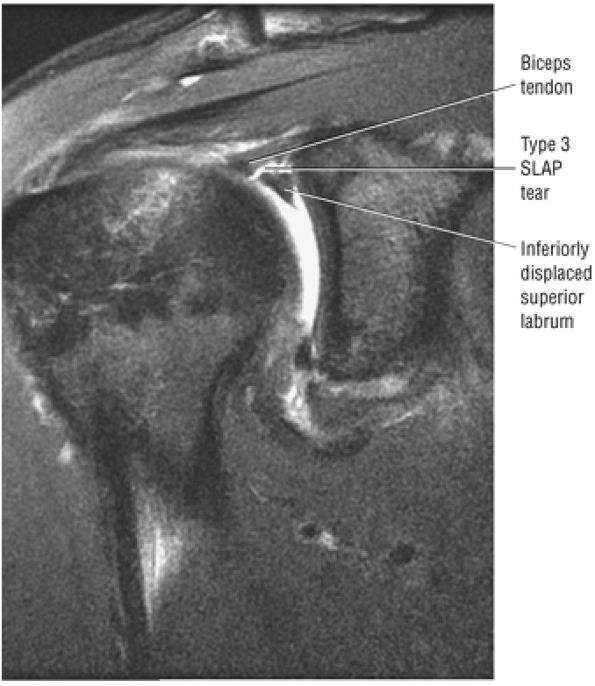

Type 2 SLAP tear extending primarily into the posterior superior labrum